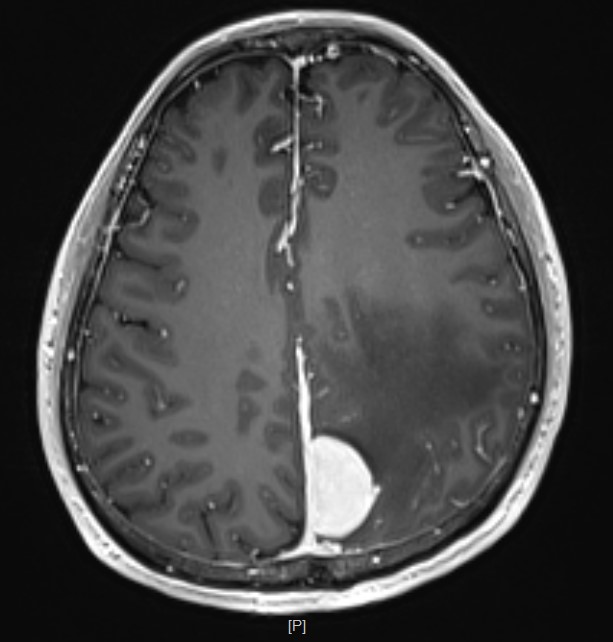

头部MR检查提示:左顶枕镰旁脑膜瘤

术后MR复查提示肿瘤切除干净